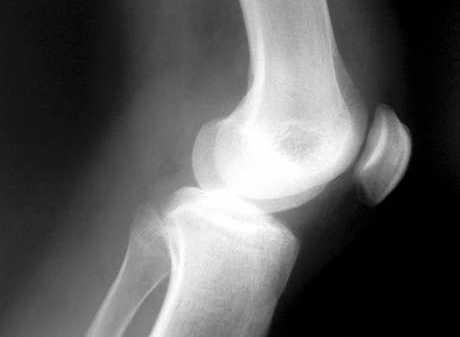

Artroza koljena u 27. godini

Poseban problem kod artroze koja se javlja u mlađoj životnoj dobi je činjenica da ona s vremenom napreduje, mijenjajući konfiguraciju zgloba te smanjujući pokretljivost pacijenta

Sve za oporavak hrskavice

Postupak koji preporučamo u pacijenata sa početnom atrozom koljena je, u početku, snaženje mišića koji okružuju koljeno. Potom slijedi dugotrajna redovita fizička rekreacija